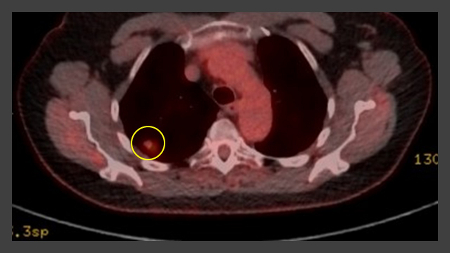

The Herder model (that incorporates F-18 fluorodeoxyglucose [FDG] avidity) has been found to be more accurate in patients who undergo positron emission tomography (PET-CT) evaluation of pulmonary nodule.[38][39] UK guidelines recommend that selected patients (pre-test probability of malignancy >10% and solid component of a nodule greater than the local threshold size [usually 8 to 10 mm]) are evaluated by PET-CT and that the Herder model is used to determine risk thereafter.[4][40]

[Figure caption and citation for the preceding image starts]: PET CT scan with 18-fluorodeoxyglucose (18-FDG) showing a low uptake in a semi-solid right upper lobe posterior lesion. Surgical resection confirmed adenocarcinoma with primarily lepidic patternFrom the collection of Dr George Tsaknis, MD, PhD, FRCP(London), MRQA, MAcadMEd, PGCert; used with permission [Citation ends].

[Figure caption and citation for the preceding image starts]: PET CT scan with 18-fluorodeoxyglucose (18-FDG) showing a high uptake peripheral left lung lesion. Surgical resection confirmed a moderately differentiated squamous cell lung cancerFrom the collection of Dr George Tsaknis, MD, PhD, FRCP(London), MRQA, MAcadMEd, PGCert; used with permission [Citation ends].